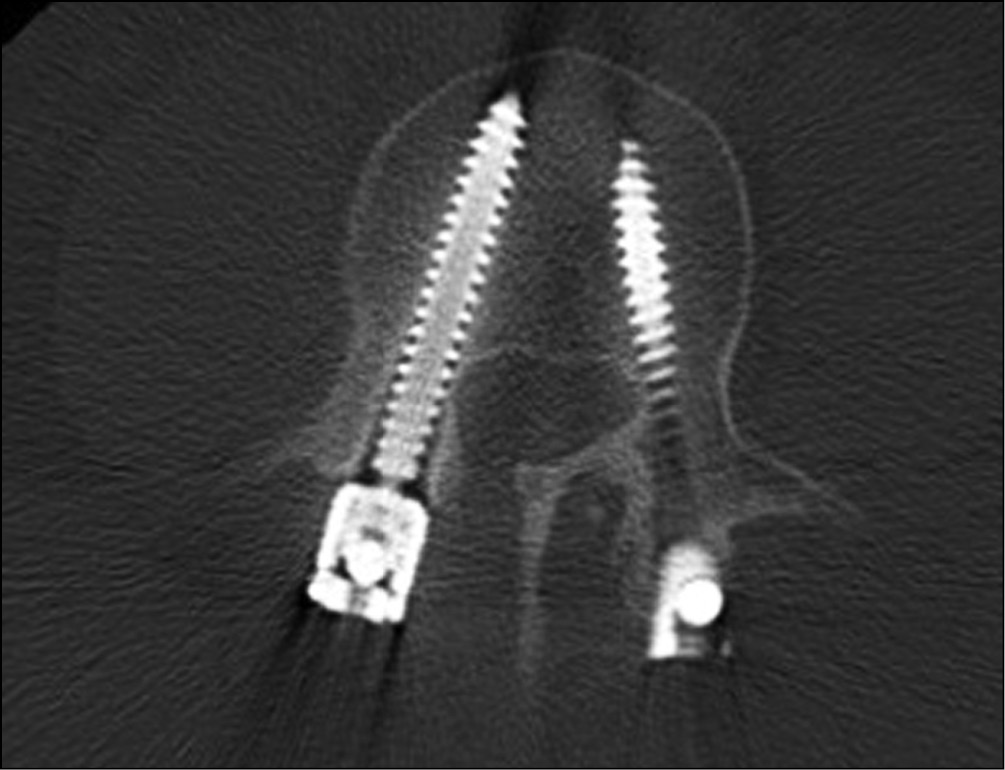

По данным КТ большая зона резорбции вокруг винтов определялась в ножках дуги позвонка, а в некоторых случаях отмечалась только в этой локализации, исключая резорбцию вокруг винта в теле позвонка (рис. 2).

Рис. 2. Резорбция костной ткани вокруг винтов в ножках дуги позвонка